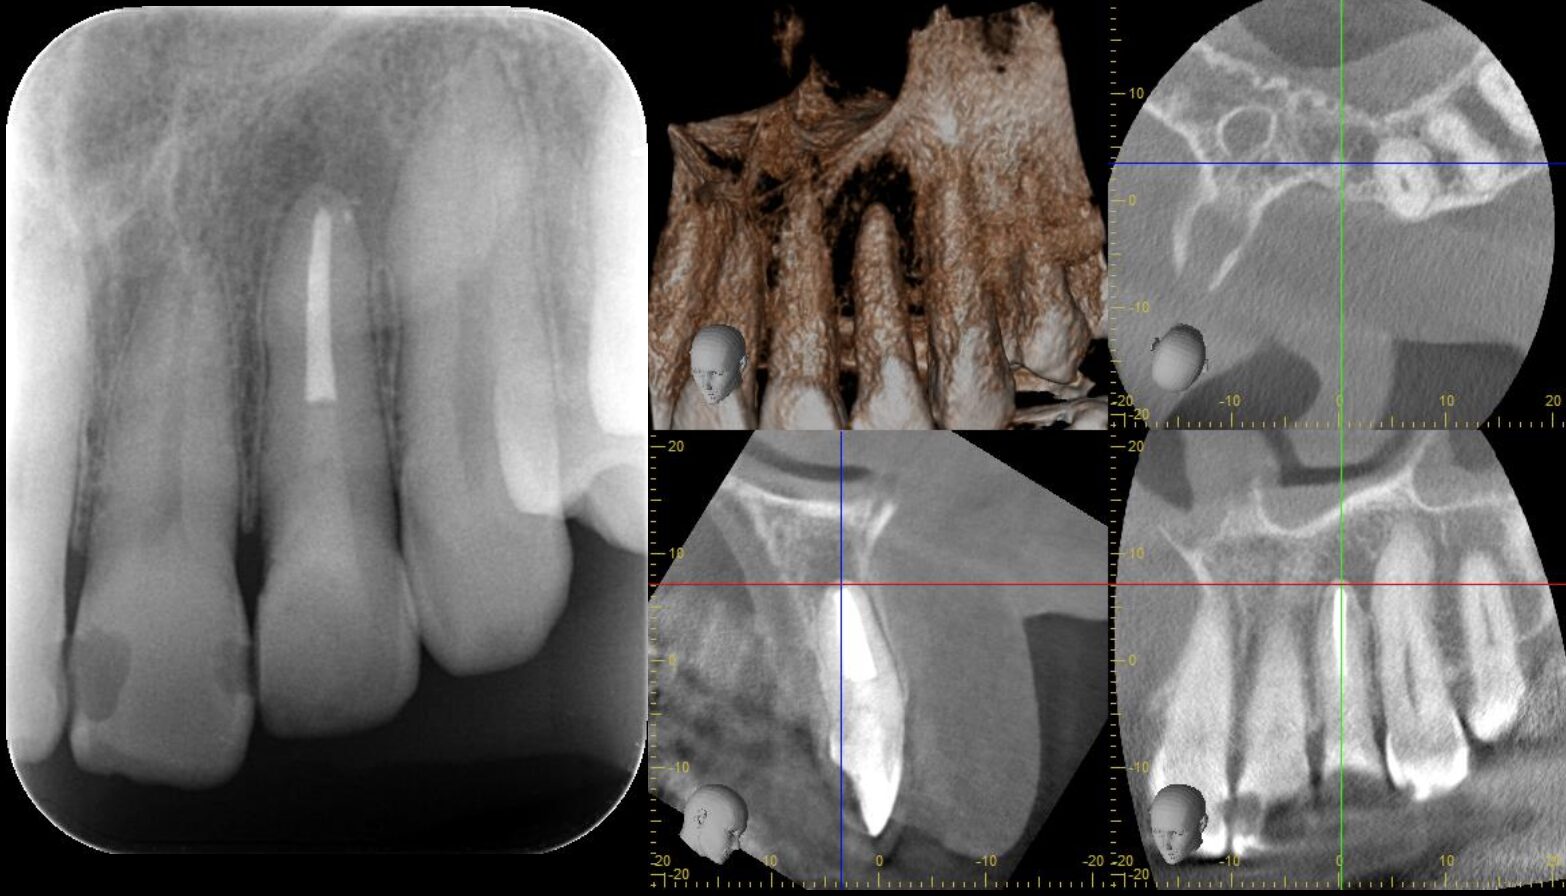

- 治療内容

- 左上側切歯

根尖性歯周炎

太くて長いメタルの土台が装着されており、CT所見では広範囲の周囲骨が炎症により破壊、吸収されている。

唇側と口蓋側の両方とも骨吸収を認め、強い炎症と反応が予測できる。

また、隣の歯にまで骨吸収が及んでいた。

3ヶ月後のCT検査で、病変の縮小と、骨の再生が認められた。

もし、治癒が認めれなければ、外科的なアプローチが必要になった症例です。

- 太くて長いメタルの土台を外す際に、健康歯質の過度な切削を起こさせないこと。

除去時にかかる力や器具操作のストレスで、歯の破折などを生じさせないように注意を払った。

土台の接着材料や、土台の種類によっては安全な除去が困難であることがあり、その場合は外科的なアプローチで病変へのアプローチをすることを、患者様と話し合った。